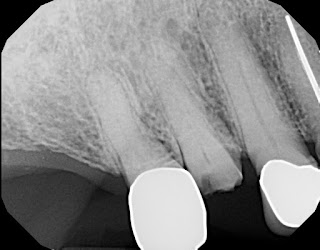

Great case from this morning. A patient came in with a tooth broken off at the gum line. A bridge was not an option due to one of the teeth, next to the broken one, already being tied into a different bridge. So an implant was chosen. We extracted the tooth. It had 2 roots. We backed filled one of the root holes with a bone graft.

Prepared the other root hole for the size and shape of the implant we wanted.

We then placed the implant. The patient came in at 9 and left by 11. We carry the most common sizes of implants on hand. If you can replace a hip, knee, or lung, you can replace a tooth. Only much easier.